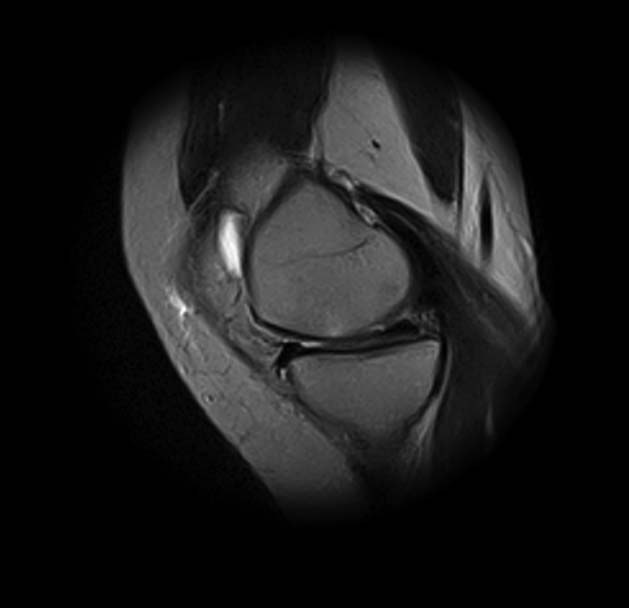

1. травма 5 лет назад - "ударилась коленом", с тех пор боли в суставе

3. стандартные рентгенограммы с небольшими изменениями - сужение

медиальной суставной щели

4. вес пациентки 80 кг, рост 165

5. сустав клинически стабилен